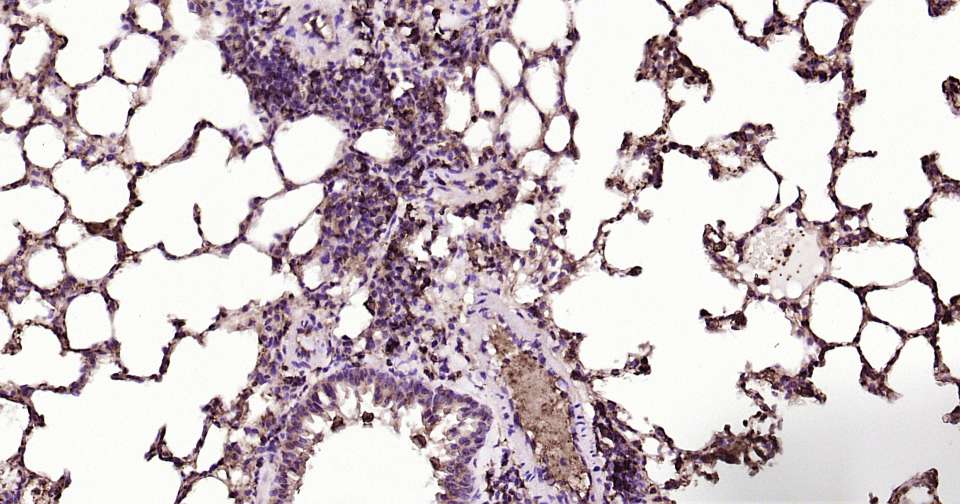

Immunohistochemical analysis of paraffin embedded mouse liver tissue slide using IHC0361M (Mouse GLUT1 Kit).

Immunohistochemical analysis of paraffin embedded mouse lung tissue slide using IHC0361M (Mouse GLUT1 Kit).